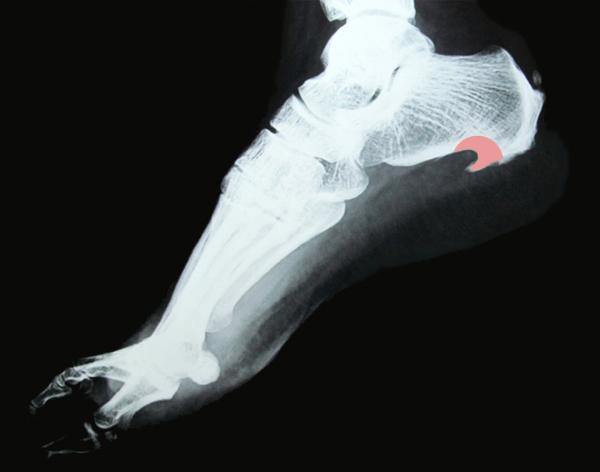

Посмотрите на изображение, демонстрирующее воспалительный процесс.

Диагностика плантарного фасциита требует тщательного обследования. В дополнение к анализу жалоб пациента, специалист должен выполнить рентгенографию, чтобы получить изображение внутренней структуры пятки.

Рентген поможет выявить наличие или отсутствие пяточной шпоры. После этих процедур важно уметь отличить плантарный фасциит от состояния, связанного с сдавлением большеберцового нерва и его ответвлений в данной области.